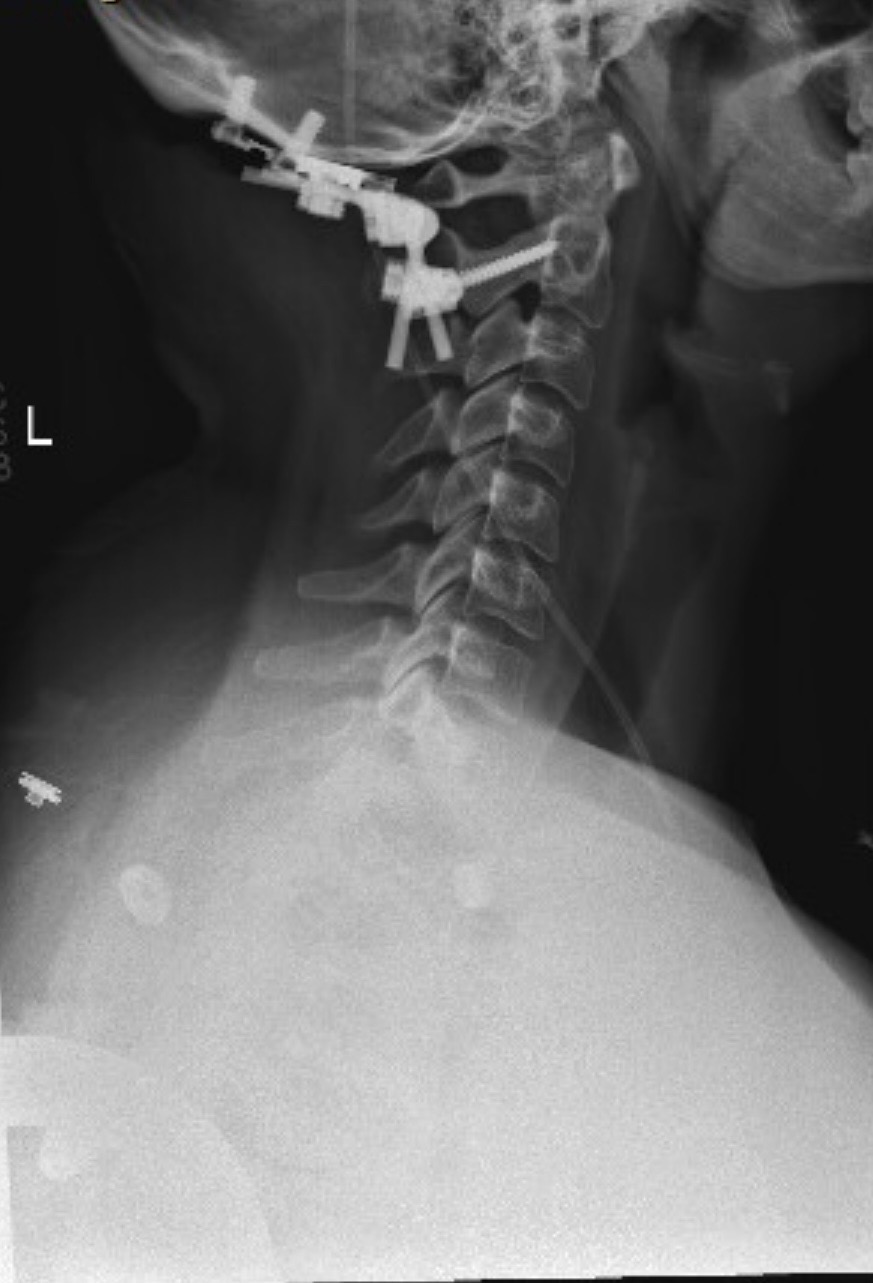

Hi everyone, my name is Savannah and I am reaching out from a place of deep vulnerability and urgent need. For years, I have lived with Ehlers-Danlos Syndrome (EDS), a challenging connective tissue disorder that has required multiple surgeries and constant management. On 2/28/24, I was rear ended in a car accident that left me with a traumatic brain injury. I was never able to fully heal from that. In October of 2024, I had a spinal surgery to relieve tension off of my low back. Recently, I underwent the most serious, life-altering procedure yet: a complex spinal fusion.

The spinal fusion was essential to stabilize my body and prevent further deterioration, but the recovery is extensive. The doctors have informed me that it will take at least one full year of healing before I can even begin to regain some independence.

Right now, my life looks drastically different. I must rely on various mobility aids and am frequently restricted to wearing a rigid neck brace to protect the surgical site. My primary focus must be rest and recovery, which makes caring for my wonderful 7-year-old daughter, Kinlee, exceptionally difficult and leaves me completely unable to work.

1. Medical Bills & Equipment: Outstanding balances from previous surgeries and costs associated with my fusion recovery (therapy, medications, durable medical equipment, and the neck brace).